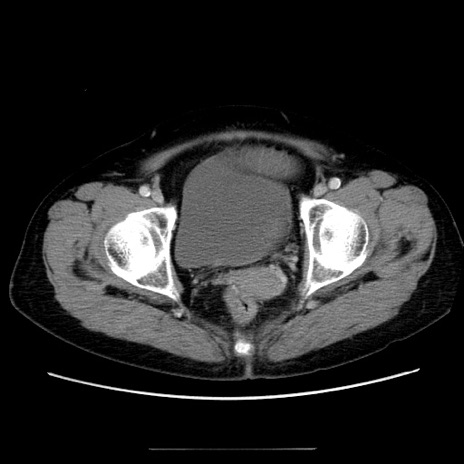

症例5(横断像)

【症例】70歳代女性

【主訴】お腹が張る

【現病歴】1週間くらい前から腹部膨満の自覚あり。昨日夜から増悪したため、本日救急外来受診。

【身体所見】意識清明、BT 36.5℃、BP 165/106mmHg、HR 80bpm、SpO2 98%、腹部:膨満、軟、自発痛・圧痛なし、触診にて不快感あり、腸蠕動音:減弱

【データ】WBC 12600、CRP 1.04